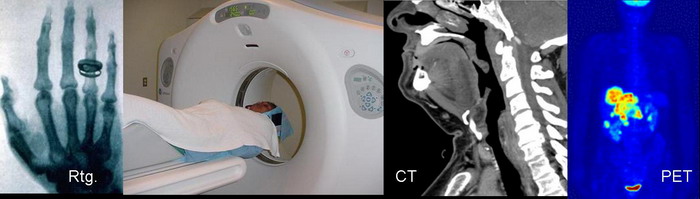

- Diagnostika v medicíne (traumatológia, onkológia, neurológia, kardiológia, psychiatria ...) a farmakológii (röntgen, CT - počítačová tomografia, PET - pozitrónová emisná tomografia)